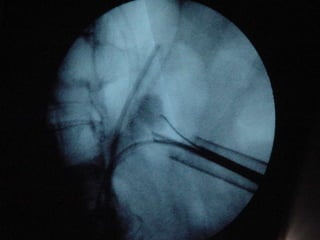

O documento discute o tratamento de urolitíase, especificamente a remoção de cálculos renais através de nefrolitotripsia. A cirurgia aberta é agora muito restrita devido aos avanços da ESWL e procedimentos endourológicos menos invasivos como ureteroscopia e cirurgia percutânea. A cirurgia laparoscópica está substituindo a cirurgia aberta como técnica menos invasiva que combina a tecnologia endourológica com a laparoscópica preservando